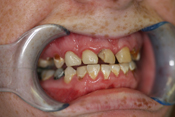

WORST TEETH Pictures from Warren Dentistry

This can happen to your teeth when proper Dental Hygiene is not practiced.

Patient 1